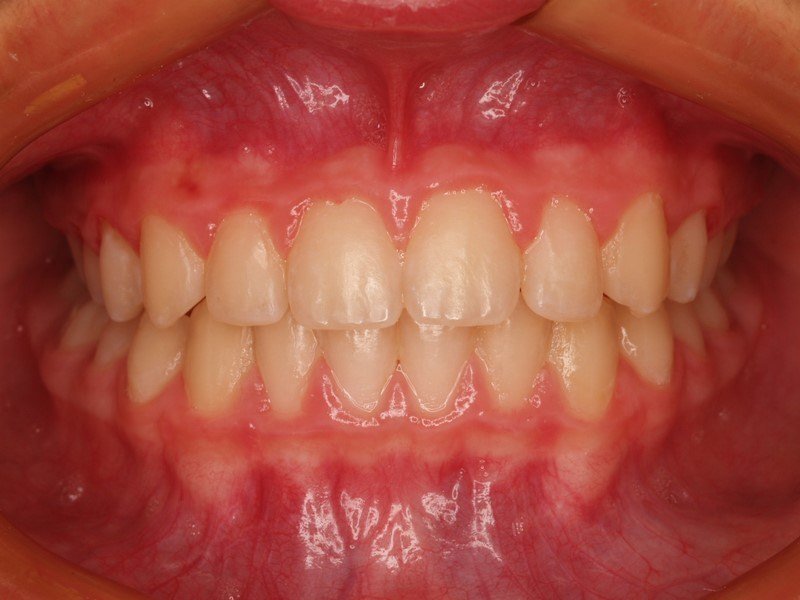

Niño de 8 años con retraso en la erupción de los dos incisivos centrales superiores y falta severa de espacio. Se trató con aparatología ortodoncica fija durante 10 meses.